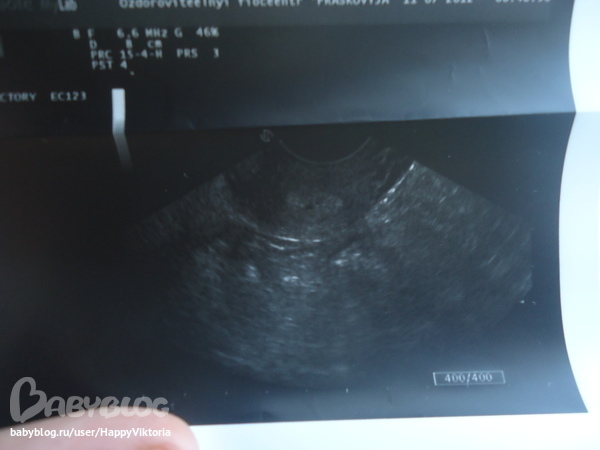

УЗИ, КТГ, доплер, скрининг, ХГЧ и другие анализыЭто многоплодная беременность?

срок очень маленький 1-2 недельки от зачатия

я вижу 2 точечки в одном пузыре,возможно у вас многоплодная беременность,и однояйцевые как у меня.Потерпите немножно и сделаете еще раз чтоб убедится.

Многоплодную можно определить не раньше 5-6 недель. Мне в 4 недели не определили двойню :)

Поддерживаю. Мне только в 6 недель увидели два плодных яйца. Но это даже еще не эмбрионы.